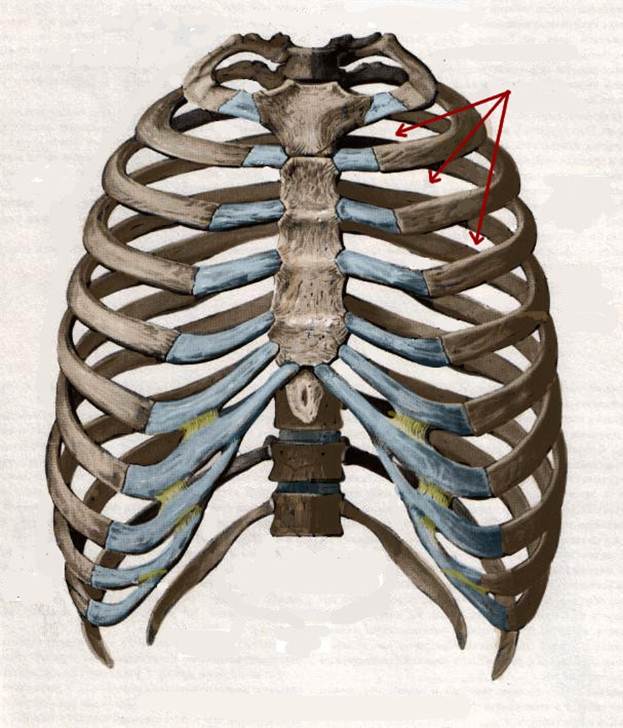

S: Стрелки указывают на сostae fluctuantes (латинский язык).